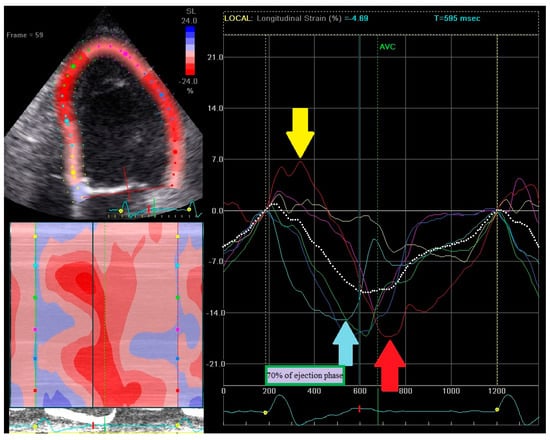

- (1)

- Early contraction of at least one basal or midventricular segment in septal or anteroseptal wall and early stretching in at least one basal or midventricular segment in the opposing wall,

- (2)

- the early peak contraction does not exceed 70% of the ejection phase,

- (3)

- the early stretching wall shows a peak contraction after aortic valve closure.